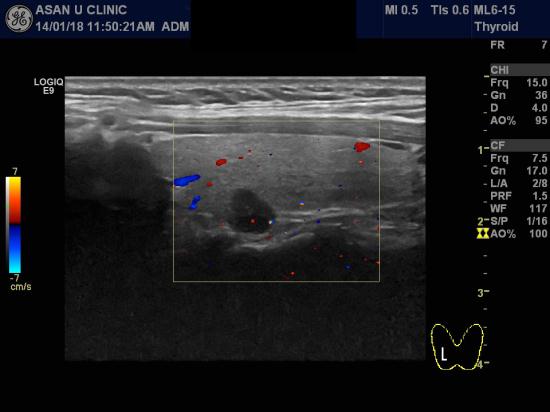

아산유외과 개원 후 17번째 갑상선암 진단.

건강검진시 우연히 발견된 갑상선우엽에 결절로

의뢰된 41세 여성입니다.

세침검사를 통해 갑상선의 유두암 진단되셨습니다.

0.7cm 의 작은 크기지만 위치가 갑상선을 덮고 있는 얇은 막과 인접해있어서

1cm이하지만 수술을 해야하는 경우입니다.